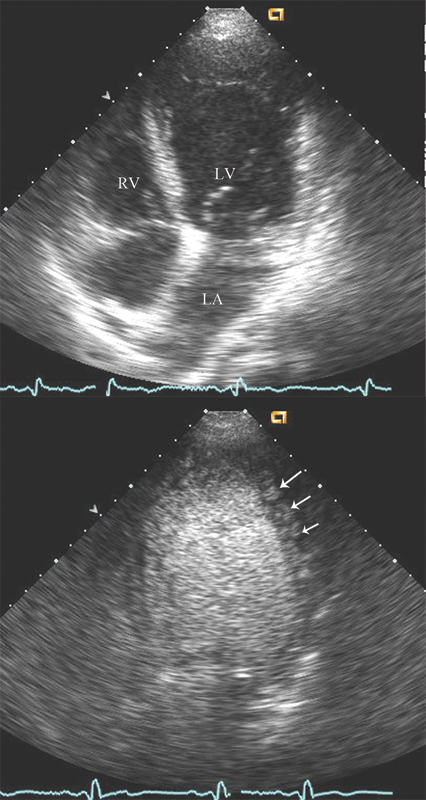

فحوصات تشخيصية لبعض امراض القلب والشرايين التاجية